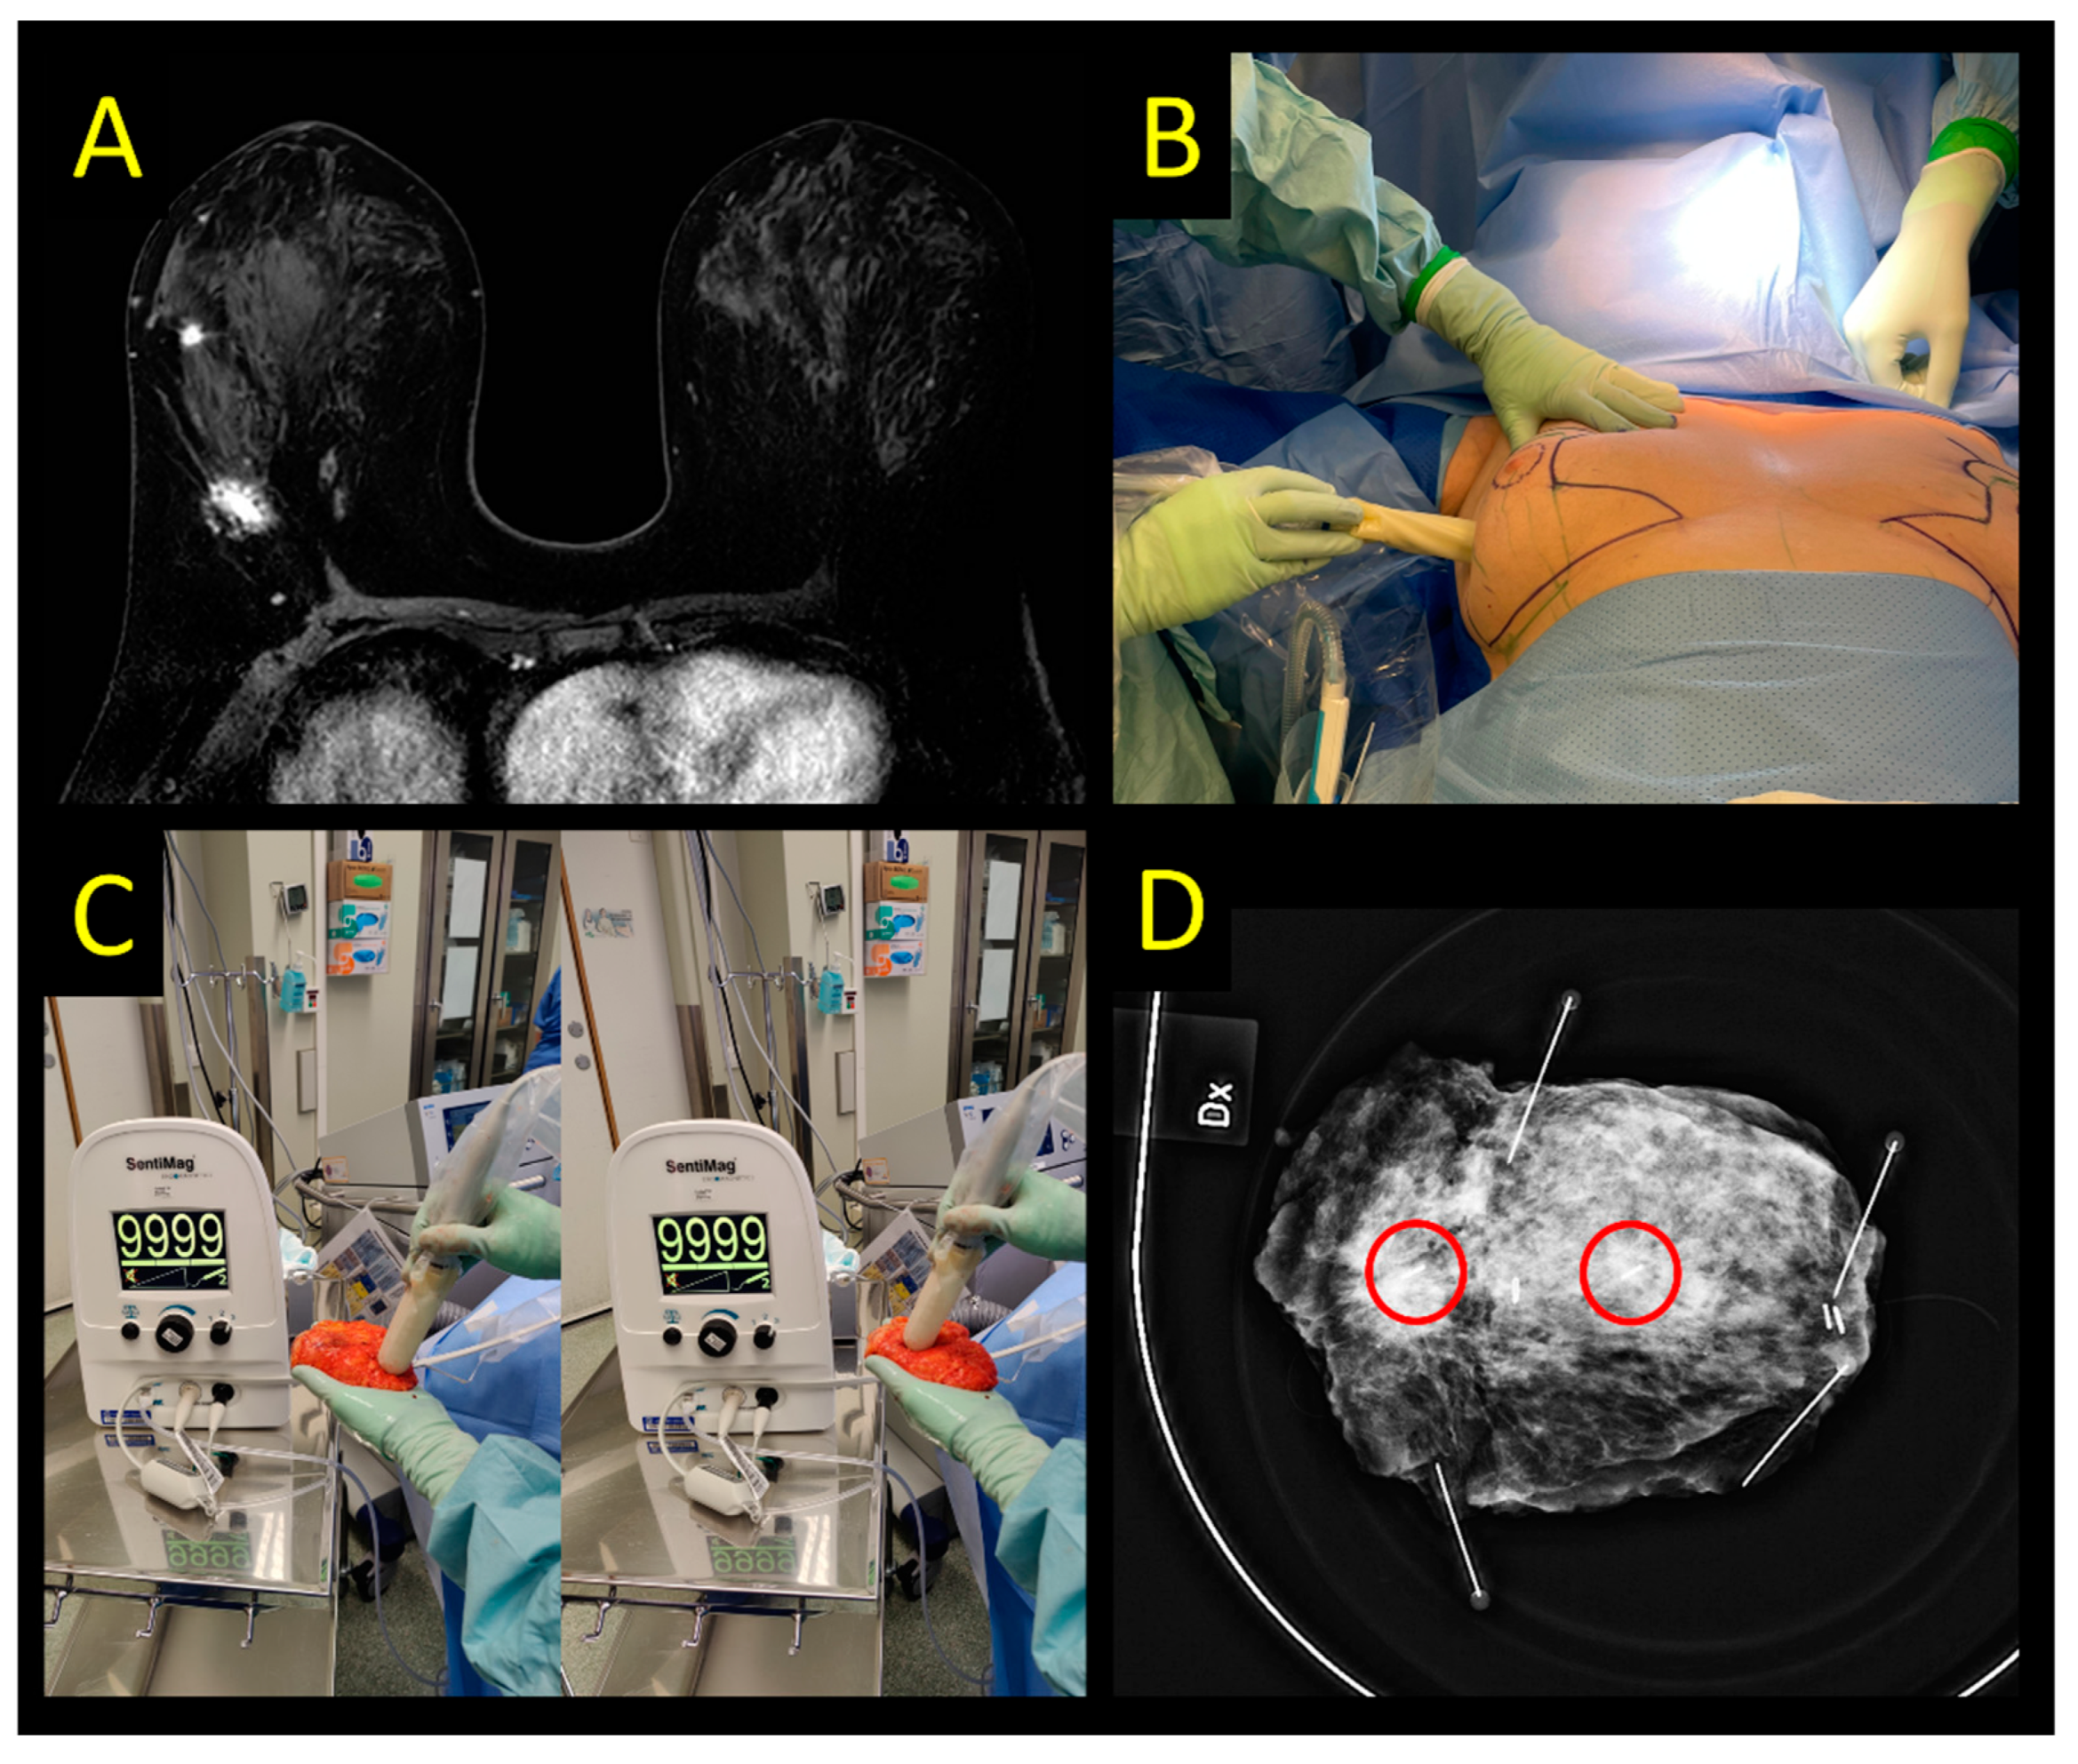

2.3. Magnetic and Paramagnetic Localization

2.4. Sirius Pintuition